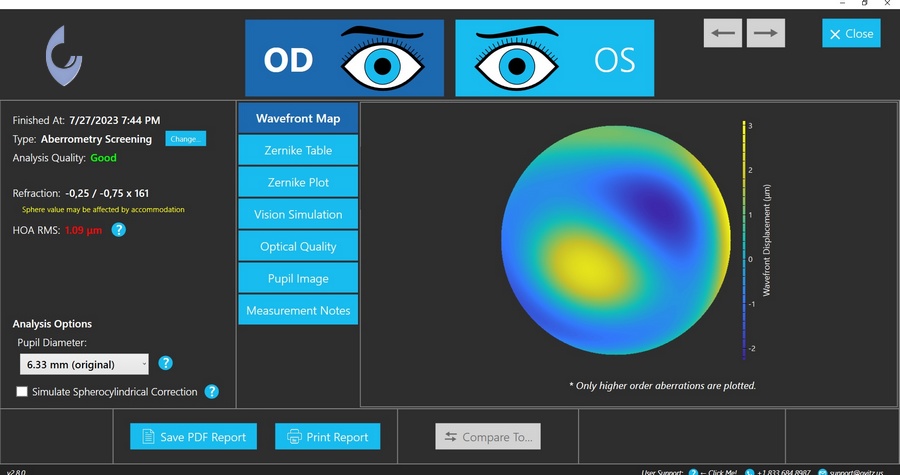

JGK gebruikt de Eye Surface Profiler (ESP) voor nauwkeurige opmeting van het oogoppervlak — inclusief het oogwit tot op 20 mm — als basis voor alle medische lensaanpassingen.